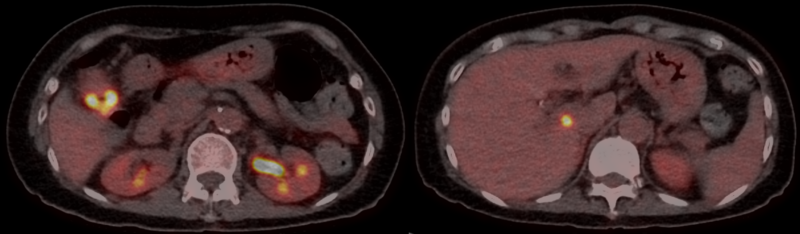

80-year-old woman presenting with cough, dysphagia, and weight loss

A 70-year-old woman with CREST syndrome on long-term mycophenolate underwent [¹⁸F]-FDG PET/CT for evaluation of a growing right lung nodule detected on high-resolution CT.

Published Date: February 6, 2026

Tags:

Abdominal

,

CT

Gastrointestinal

Pathology

PET